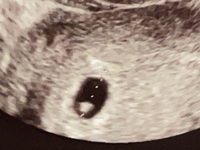

1(結論)5w5dの胎嚢の平均サイズは13mm。最小は65mm、最大は21mmでした 出産できた40人:5w5dの胎嚢平均サイズは13mm 出産できた40人(体外受精15人、AIH1人、その他自然妊娠)の胎嚢サイズを比較したところ、 平均サイズは13mm という結果でし 胎嚢の成長速度や大きさの目安・平均値は? 胎嚢は 1日で約1ミリ 成長するといわれています。 平均的な成長速度と比べて、胎嚢の成長スピードがあまりに遅い・胎嚢が小さい場合は稽留流産(けいりゅうりゅうざん)などの可能性が出てきます。

胎嚢 平均の大きさ- 5w1d胎嚢の平均サイズは775mm妊婦30人比較結果 1 5w3d出産できた妊婦34人の胎嚢の大きさの平均は109mm。 一番大きい人で172mm、一番小さい人は50mm(双子。 単胎は63mm)でした。 結論:5w3dで胎嚢確認できた妊婦40人の平均は103mmでした。 ただし、その後出産できた34人に限ると胎嚢の大きさの平均は109mmでした。 逆に、流産してしまった6 2 4w5dの胎嚢の大きさは平均4mm(出産できた妊婦31名の実績調査)。4w5dの時点では、その後流産した人たちとの胎嚢サイズに大差はありません 出産できた妊婦さん31人の、 4w5dの胎嚢の平均的な大きさ

胎嚢の大きさ・頭殿長の大きさ 胎嚢の大きさと妊娠数週は以下のとおりです。 胎嚢の大きさ・頭殿長の大きさの平均値がわかります。 最大胎嚢径(GS) 頭殿長(CRL) cm 平均 範囲 cm 平均 範囲 10 4w5d 4w2d5w2d 10 7w4d 7w1d8w1d 11 4w6d 4w3d5w3d 11 7w5d 7w2d8w2d胎嚢の平均サイズ 平均的な胎嚢の大きさ 妊娠6週:平均約147mm(最小約94mm~最大約210mm) 妊娠7週:平均約213mm(約149~2mm) 妊娠8週:平均約2mm(約8mm~369mm) 妊娠9週:平均約353m 胎嚢の成長速度や大きさの目安・平均値は? 胎嚢の大きさ:平均193mm 胎芽の大きさ:平均32mm 心拍確認まだの人(13人) 胎嚢の大きさ:平均132mm 胎芽の大きさ:平均17mm